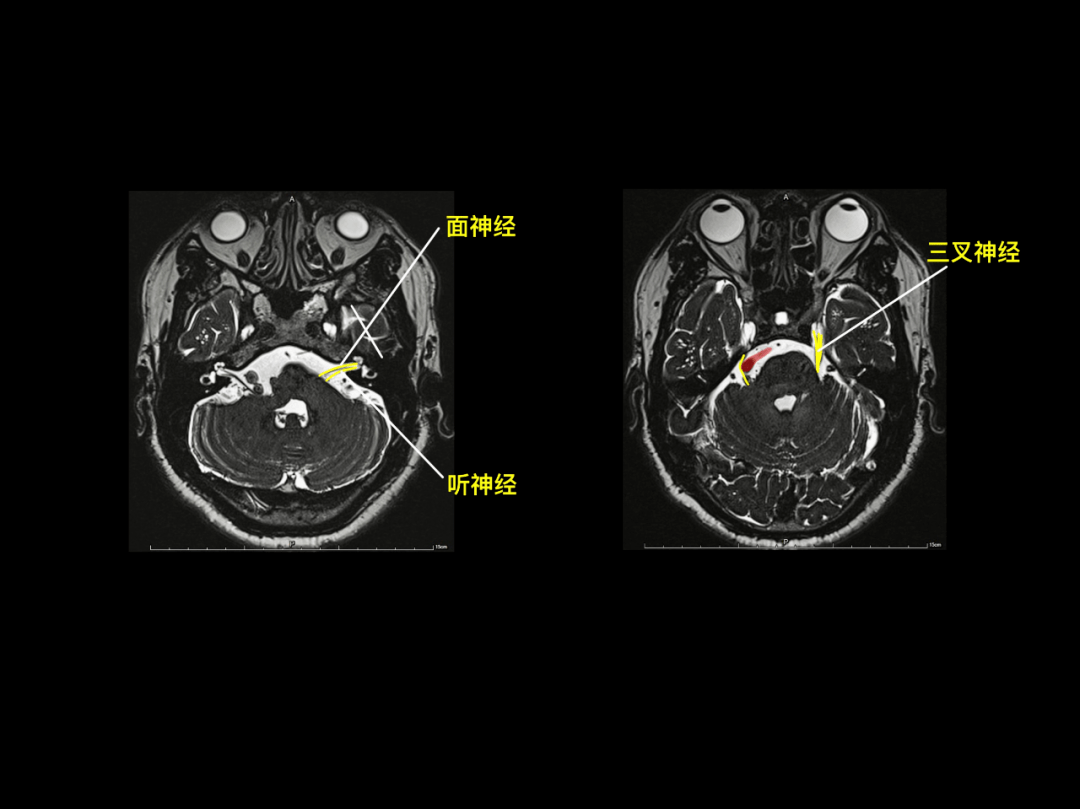

头颅mr横断面解剖中英文对照版,音乐 影像 解剖原来是另一番新天地

颅脑mr阅片手绘二徐桂兴博士

超棒颅脑mr阅片手绘版来啦

脑干:延髓,脑桥,中脑海马脑叶,基底节区额下回,颞